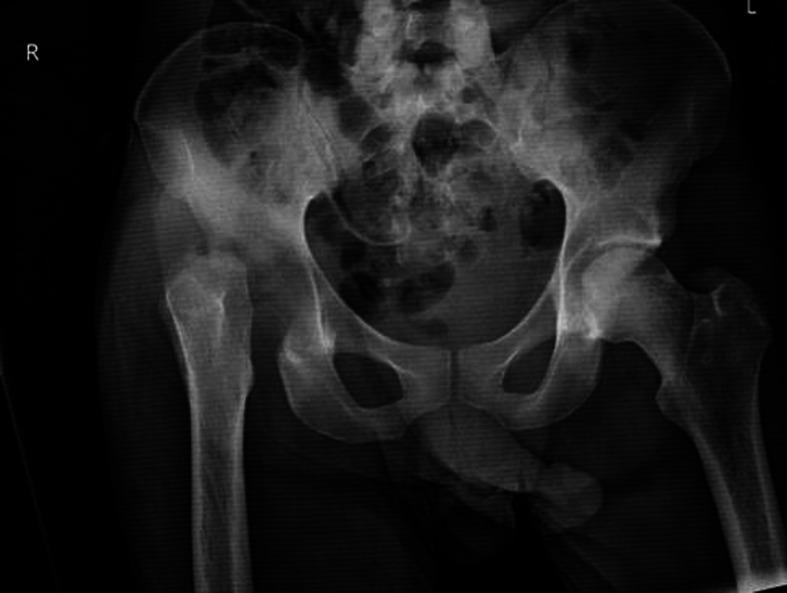

Unilateral avascular necrosis of the right hip in an HIV patient with tearing of the rectus femoris and adductor longus muscles.

A man in his 20s with a medical history of syphilis, chlamydia and HIV presented to the emergency department (ED) with 2 months of right hip pain and was found to have advanced avascular necrosis (AVN) of the right femoral head with secondary haemorrhage. The patient lacked the common risk factors of AVN in patients with HIV (PWH): ≥10 years of HIV diagnosis, extended duration on highly active antiretroviral therapy, trauma, corticosteroid use, alcohol abuse, systemic lupus erythematosus, obesity, smoking and dyslipidaemia. Given the extensive destructive changes in the hip joint and muscles, a right hip resection arthroplasty was performed, and the patient recovered well postoperatively. This case presents a learning opportunity for understanding bone pathologies in PWH and offers clinical guidance for the management of HIV-infected patients with a focus on optimising bone health.